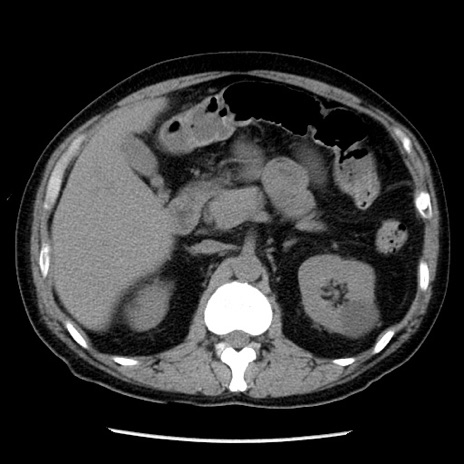

症例29(横断像)

【症例】40歳代男性

【現病歴】2日前から胃痛あり。徐々に周期的な激痛に変化した。本日になっても激痛があるため受診。

【身体所見】意識清明、BT 38-39℃台あり、腹部:膨満、やや硬、右下腹部に圧痛あり。

【データ】WBC 8500、CRP 23.26